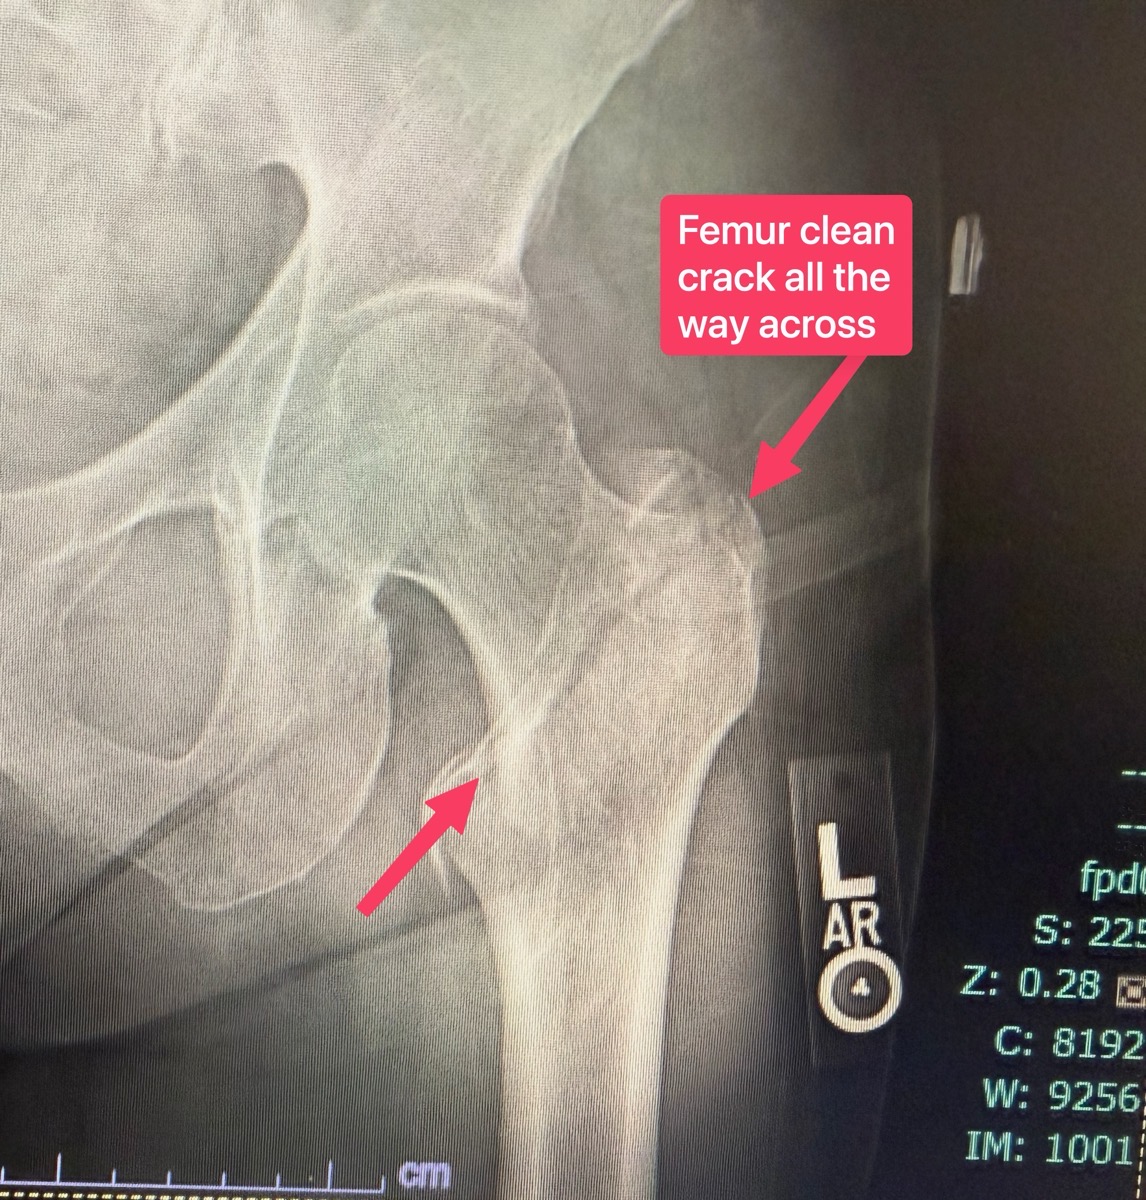

That’s pretty much the end of the tech part of what happened, unless you want to see X-rays of what happened. The femur bone is the long bone from your knee up to your hip, with the ball on top that rotates around in the socket of your pelvis. The X-rays showed that there was a clean break diagonally across the bone. It’s below the ball, and goes from the lesser to greater tranchanter.

To fix it, the surgeon drilled a vertical hole down into the shaft of the femur to put in a rod, and then put a screw across the break through the rod to pull the two pieces together. Another screw goes sideways into the rod through my bone to stabilize the rod from rotating. The surgeon told me that it was a good break in that the bones did not shift, so he was able to “just” bolt me back together to hold things in place until the bone heals back together.